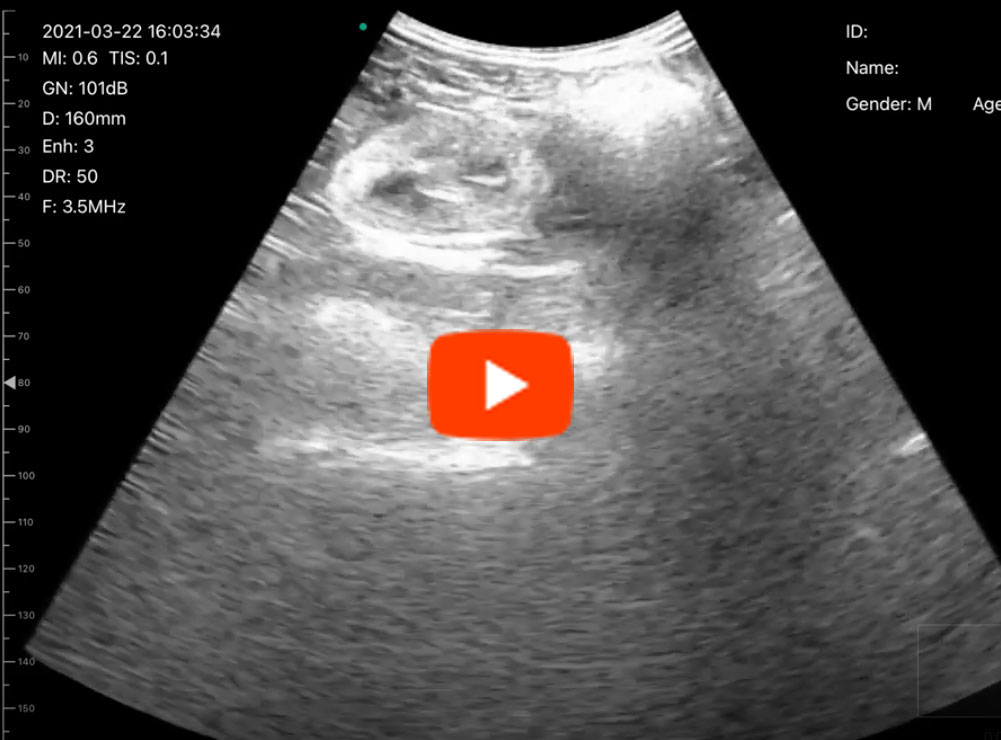

C6C動画1

C6C動画2

C6C動画3

C6C動画4